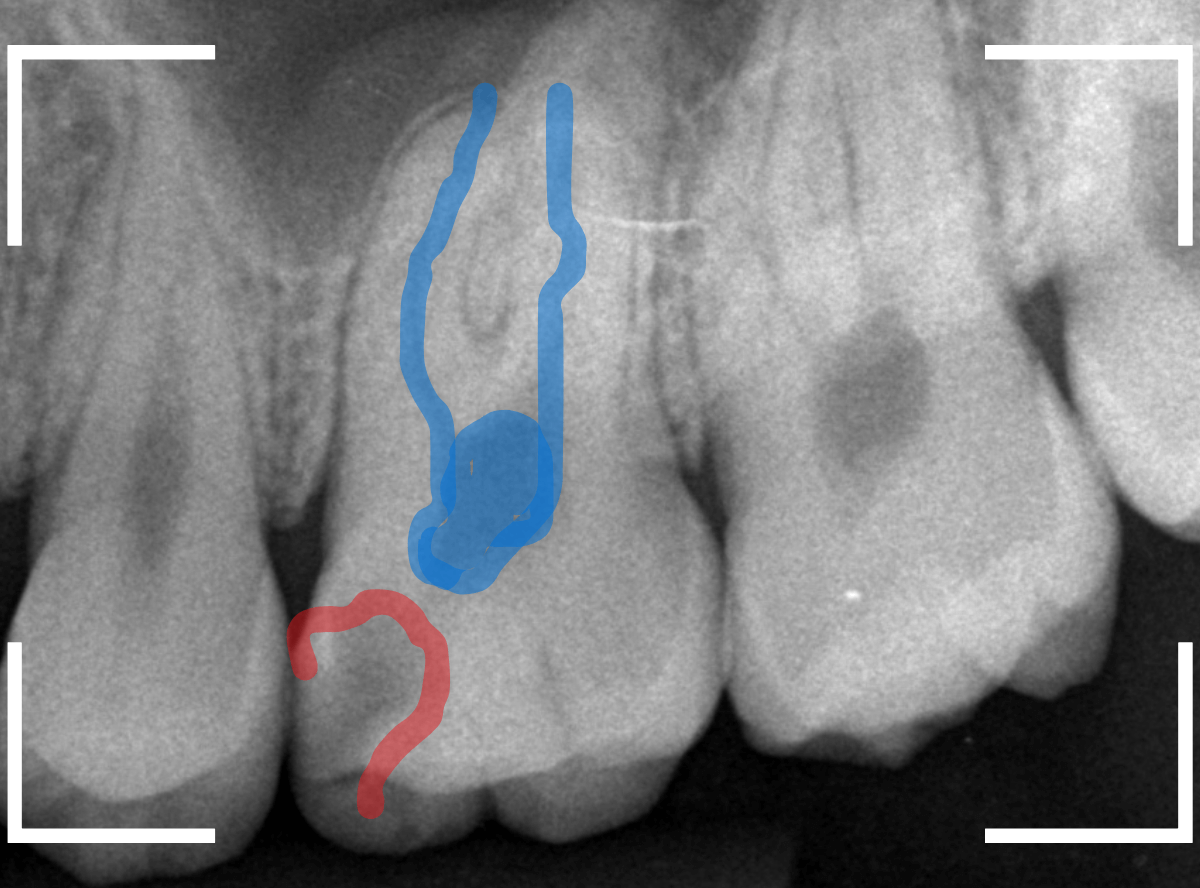

Case.18 おやしらずの抜歯後に歯がしみる

今回は、上のおやしらずが原因で虫歯になってしまった方のケースです。

〇部のおやしらずを虫歯で抜歯しました。

レントゲン写真です。

レジンの下が虫歯になっているのがわかります。

抜歯してしばらく経ったところです。

特に問題なさそうに見えますが、「おやしらずを抜歯してから、歯がしみるようになった」との訴えです。

これは、おやしらずを抜歯した後によくある症状です。

レントゲン写真で確認します。

青い線が歯の神経、赤い線が虫歯です。

おやしらずがあった際にはわかりづらかったですが、歯の後ろ側のおやしらずが重なっていたところが虫歯になっているのがわかります。

おやしらずが原因で、このように手前の歯が虫歯になってしまう事が多いために、抜歯を勧められる事が多いのです。

そして、虫歯の部分におやしらずが被さっていたために、しみる症状などを感じなかったのです。